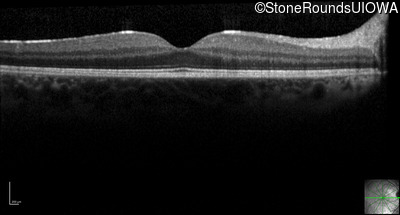

Optical Coherence Tomography - Left - 20/20 -1

Exemplar / OCT Stack